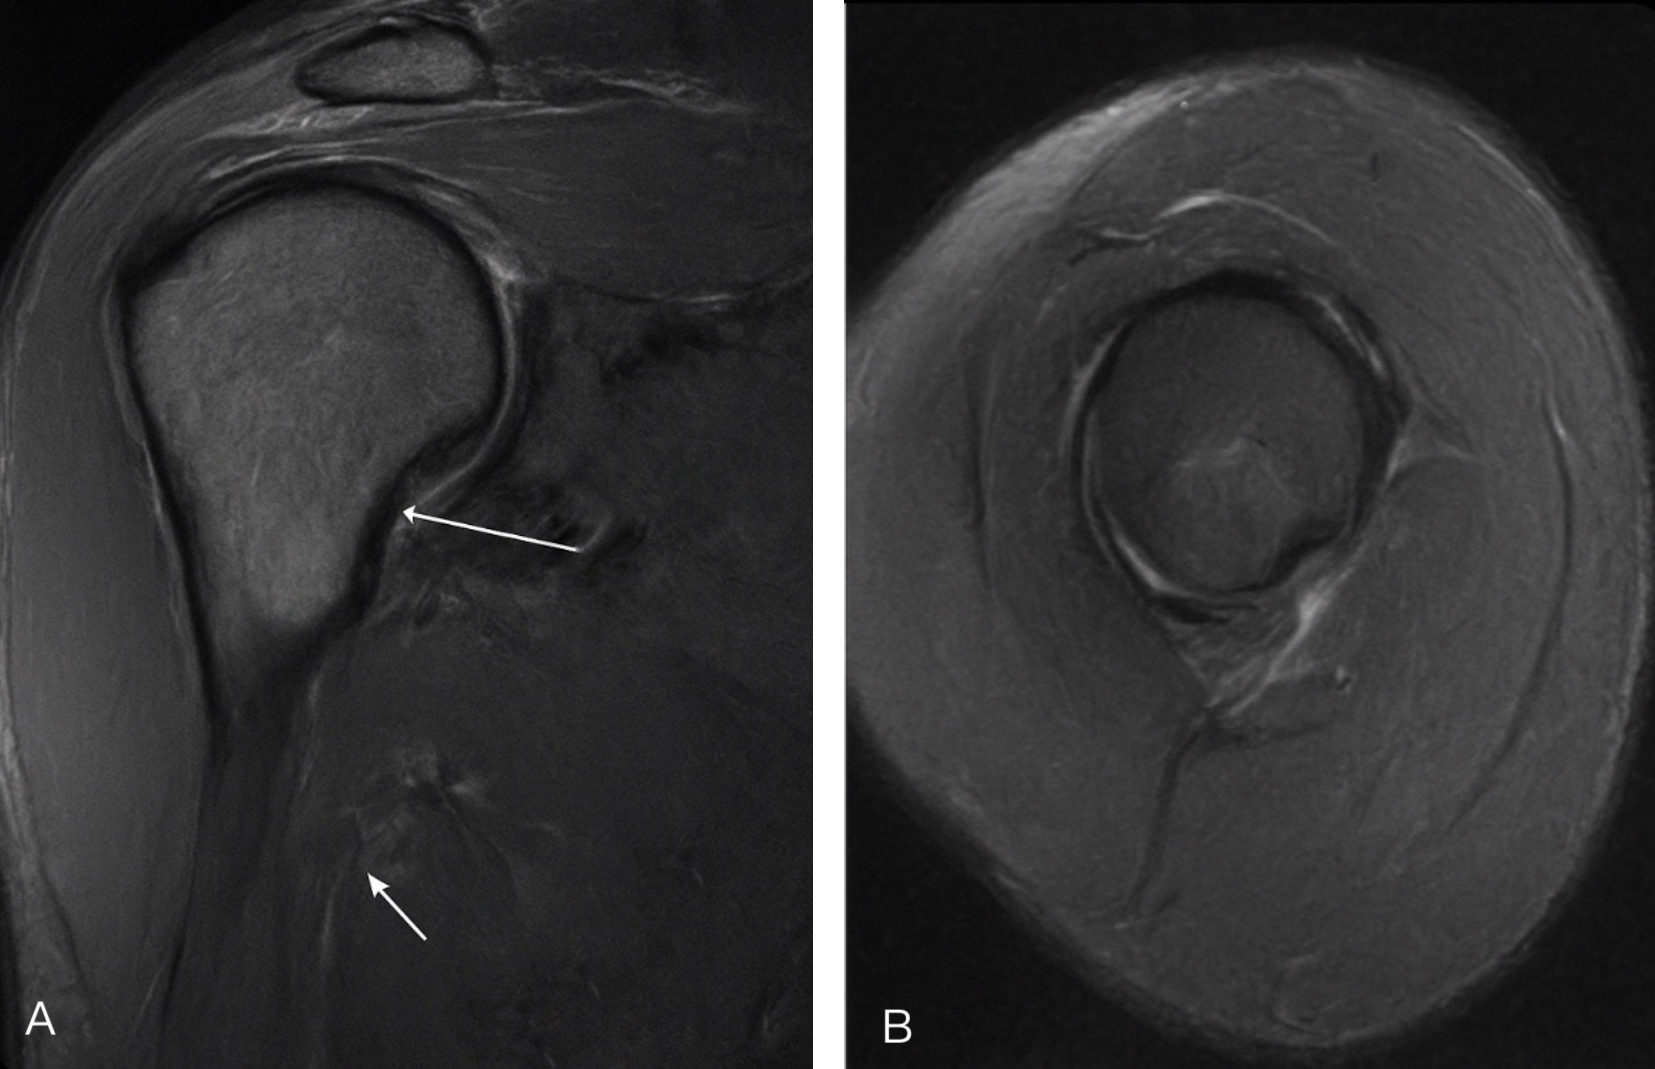

Magnetic resonance imaging (MRI) revealed an intrasubstance tear of the upper one-third of the subscapularis tendon consistent with a Lafosse IIA lesion (Figure 1). The tear was confined to the tendon substance without detachment from the lesser tuberosity. The supraspinatus, infraspinatus, and teres minor tendons were intact, and no associated biceps pulley injury was observed.